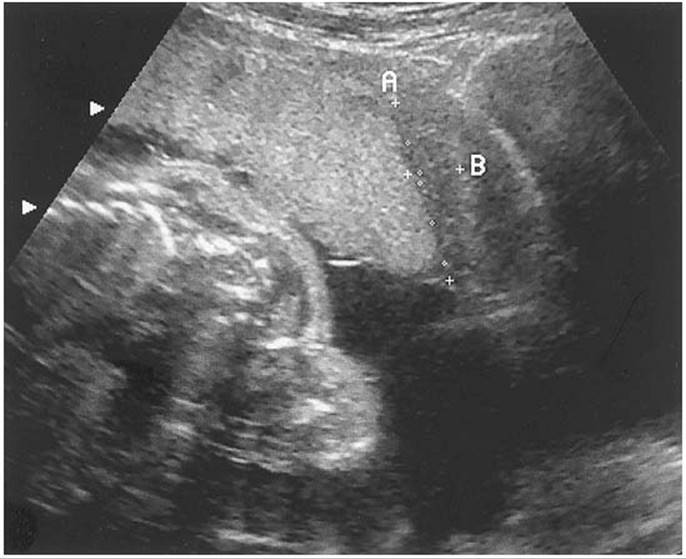

Although initially thought to be contraindicated in patients with suspected placenta previa, transvaginal scanning can be safely performed with caution. In many cases, the relationship between the placental edge and the internal os can be difficult to assess and only a close-up view with a transvaginal approach can make a definitive diagnosis (Fig. 20.3). This approach to scanning has been studied carefully and it does not appear to lead to increased vaginal bleeding, in part because it is technically impossible to introduce the probe through the cervix. Another alternative approach is with translabial scanning which has been reported to be 100% sensitive for detection of a previa. However, on occasion, bowel gas can interfere. When a clear diagnosis of placenta previa is made by a transabdominal or translabial scan, there is no need to perform a transvaginal scan. However, when a partial/marginal placenta previa or low-lying placenta is suspected, a transvaginal scan should be performed to confirm the diagnosis and the distance between the internal os and lower placental edge should be determined. Both types of scanning have greatly reduced the false-positive rate by transabdominal scanning alone which is reported to be as high as 25%.

FIG. 20.5. A transvaginal color Doppler ultrasound image of a suspected vasa previa. Markers indicate the distance between the internal os and the cord insertion into the membranes away from the placental edge, a distance less than 1 cm. See color figure 20.5.